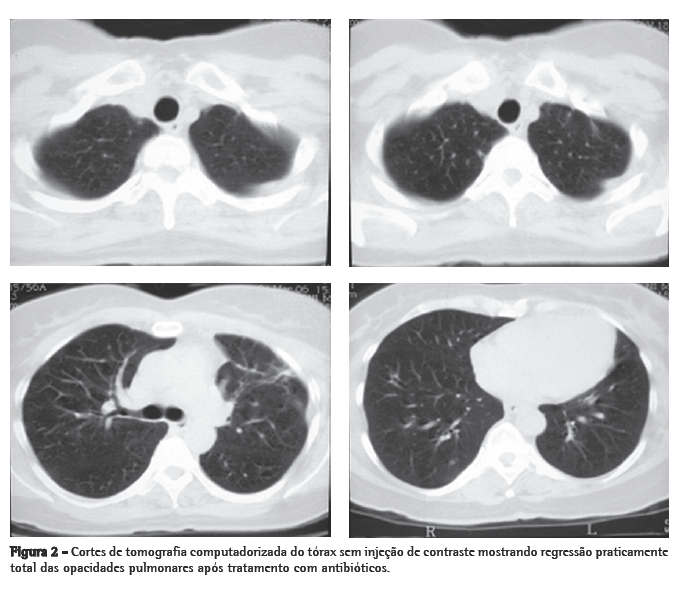

Mulher de 56 anos, branca, procurou o serviço de emergência devido à tumoração em região cervical à direita, dolorosa, há 5 dias. Apresentava tosse seca e febre alta há 3 dias. Negava tabagismo. Era hipertensa e diabética e havia tido um infarto do miocárdio há 3 anos. Na admissão, a paciente apresentava-se desidratada, afebril (temperatura axilar, 36,7°C), eupnéica, com tumoração cervical dolorosa à direita. Os exames laboratoriais revelaram velocidade de hemossedimentação aumentada (92 mm). A ecografia cervical mostrou trombose em VJI direita, sendo iniciada anticoagulação no quarto dia de internação. A radiografia de tórax demonstrou pelo menos dois nódulos no pulmão esquerdo, um aparentemente escavado e outro com 18 mm de diâmetro na base, além de lesão irregular com 25 mm de diâmetro no lobo superior direito. Foi realizado ecocardiograma transesofágico para descartar a hipótese de endocardite, o qual não demonstrou presença de vegetações. Devido à hipótese de pneumonia, foi iniciado tratamento empírico com 500 mg de cefuroxima, via oral, a cada 12 h. A tomografia de tórax revelou múltiplas opacidades bilaterais, de aspecto sugestivo de implante metastático (Figura 1). Prosseguindo a investigação, a paciente foi submetida à broncoscopia flexível, cujos achados endoscópicos foram normais. A análise microbiológica do lavado broncoalveolar para pesquisa de bacilo álcool-ácido resistente e fungos, assim como seu estudo citopatológico e culturas, foram negativos. Com a hipótese de neoplasia metastática, a paciente foi submetida à biópsia pulmonar cirúrgica, cujo exame anatomopatológico mostrou inflamação supurativa crônica abscedada em organização em parênquima pulmonar. Frente à hipótese de síndrome de Lemierre devido à trombose jugular associada à embolia séptica pulmonar, a paciente foi questionada sobre a ocorrência de amigdalite no início do quadro. A paciente não recordava, mas a filha lembrou que a mesma havia usado 500 mg de amoxicilina, via oral, a cada 8 h por 10 dias, para tratamento de amigdalite alguns dias antes da internação. Na admissão hospitalar, a paciente recebeu um curso de cefuroxima (750 mg endovenoso a cada 8 horas por 7 dias) concomitante a azitromicina (500 mg via oral por 5 dias),que, por persistência da febre, foi modificado para cefepime (1.000 mg a cada 12 horas por 7 dias).

A tomografia computadorizada de tórax de controle após este curso de antibióticos mostrou regressão praticamente total das opacidades (Figura 2). Permaneceu afebril desde o terceiro dia do novo curso de antibióticos. Nenhum microrganismo foi isolado das hemoculturas e culturas do lavado broncoalveolar. A anticoagulação foi suspensa após 20 dias de uso, pela falta de evidência de benefício na síndrome de Lemierre.